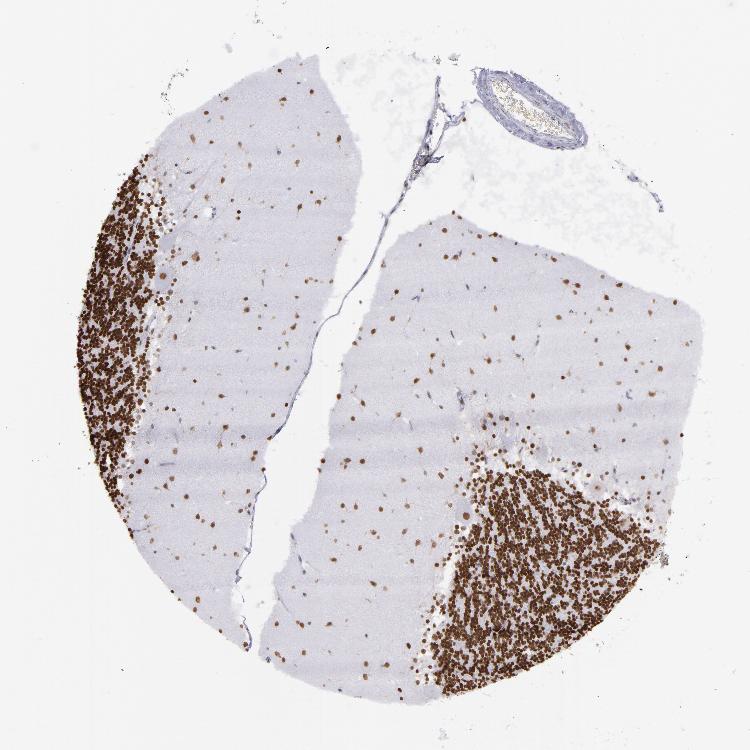

BRAIN CEREBELLUM Show tissue menu

CEREBELLUM - Expression summary

CEREBELLUM - Antibody stainingi

Antibody staining in the annotated cell types in the current human tissue is reported as not detected, low, medium, or high, based on conventional immunohistochemistry profiling in selected tissues. This score is based on the combination of the staining intensity and fraction of stained cells.

Each image is clickable and will lead to virtual microscopy that enables deeper exploration of all samples and also displays staining intensity scores, fraction scores and subcellular localization as well as patient and tissue information for each sample.

Antibody HPA001907Antibody HPA002735Antibody CAB010451Antibody CAB080271

Purkinje cells MediumMediumMediumLow

Cells in granular layer HighMediumMediumHigh

Cells in molecular layer HighMediumMediumHigh